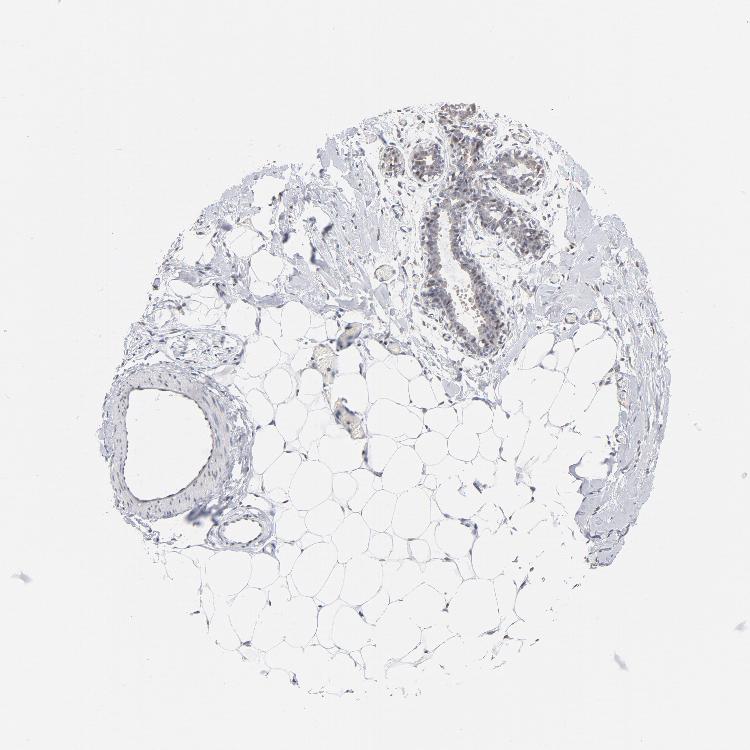

BREAST - Antibody stainingi

Antibody staining in the annotated cell types in the current human tissue is reported as not detected, low, medium, or high, based on conventional immunohistochemistry profiling in selected tissues. This score is based on the combination of the staining intensity and fraction of stained cells.

Each image is clickable and will lead to virtual microscopy that enables deeper exploration of all samples and also displays staining intensity scores, fraction scores and subcellular localization as well as patient and tissue information for each sample.

Antibody HPA003624Antibody CAB062559

Adipocytes LowNot detected

Glandular cells LowLow

Myoepithelial cells Not detectedNot detected